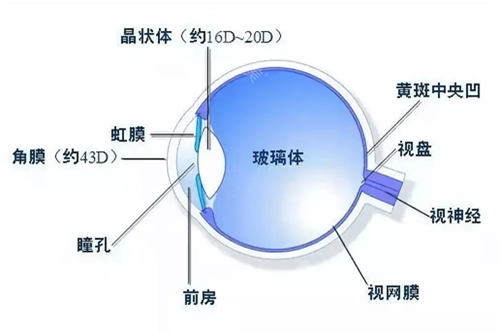

白内障专科:准屈光性手术

邵杰医师在白内障超声乳化联合功能性人工晶体植入方面经验充足,能够根据患者用眼需求定制散光矫正型、三焦点等个性化晶体,术后脱镜率高达92%。李凌副高医师则擅长糖尿病视网膜病变合并复杂白内障的联合手术,术后视力达标率优异。

特色技术:医院开展的微切口超声乳化手术,切口仅1.8mm,术后改善比较快,第二天即可获得良好视力。